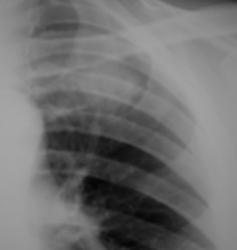

Исследование проведено на цифровом флюорографе «Ренекс-Флюоро». Иллюстрация 1 – прямая проекция. Иллюстрации 2, 3 – изучение изображения с увеличением.

Иллюстрация 2. Создается впечатление нечеткости контуров фокусной тени, неоднородность ей структуры. Имеет место некоторое расширение и гомогенизация тени левого корня.

Иллюстрация 3. Визуализируется «дорожка» к корню левого лёгкого от фокусной тени.